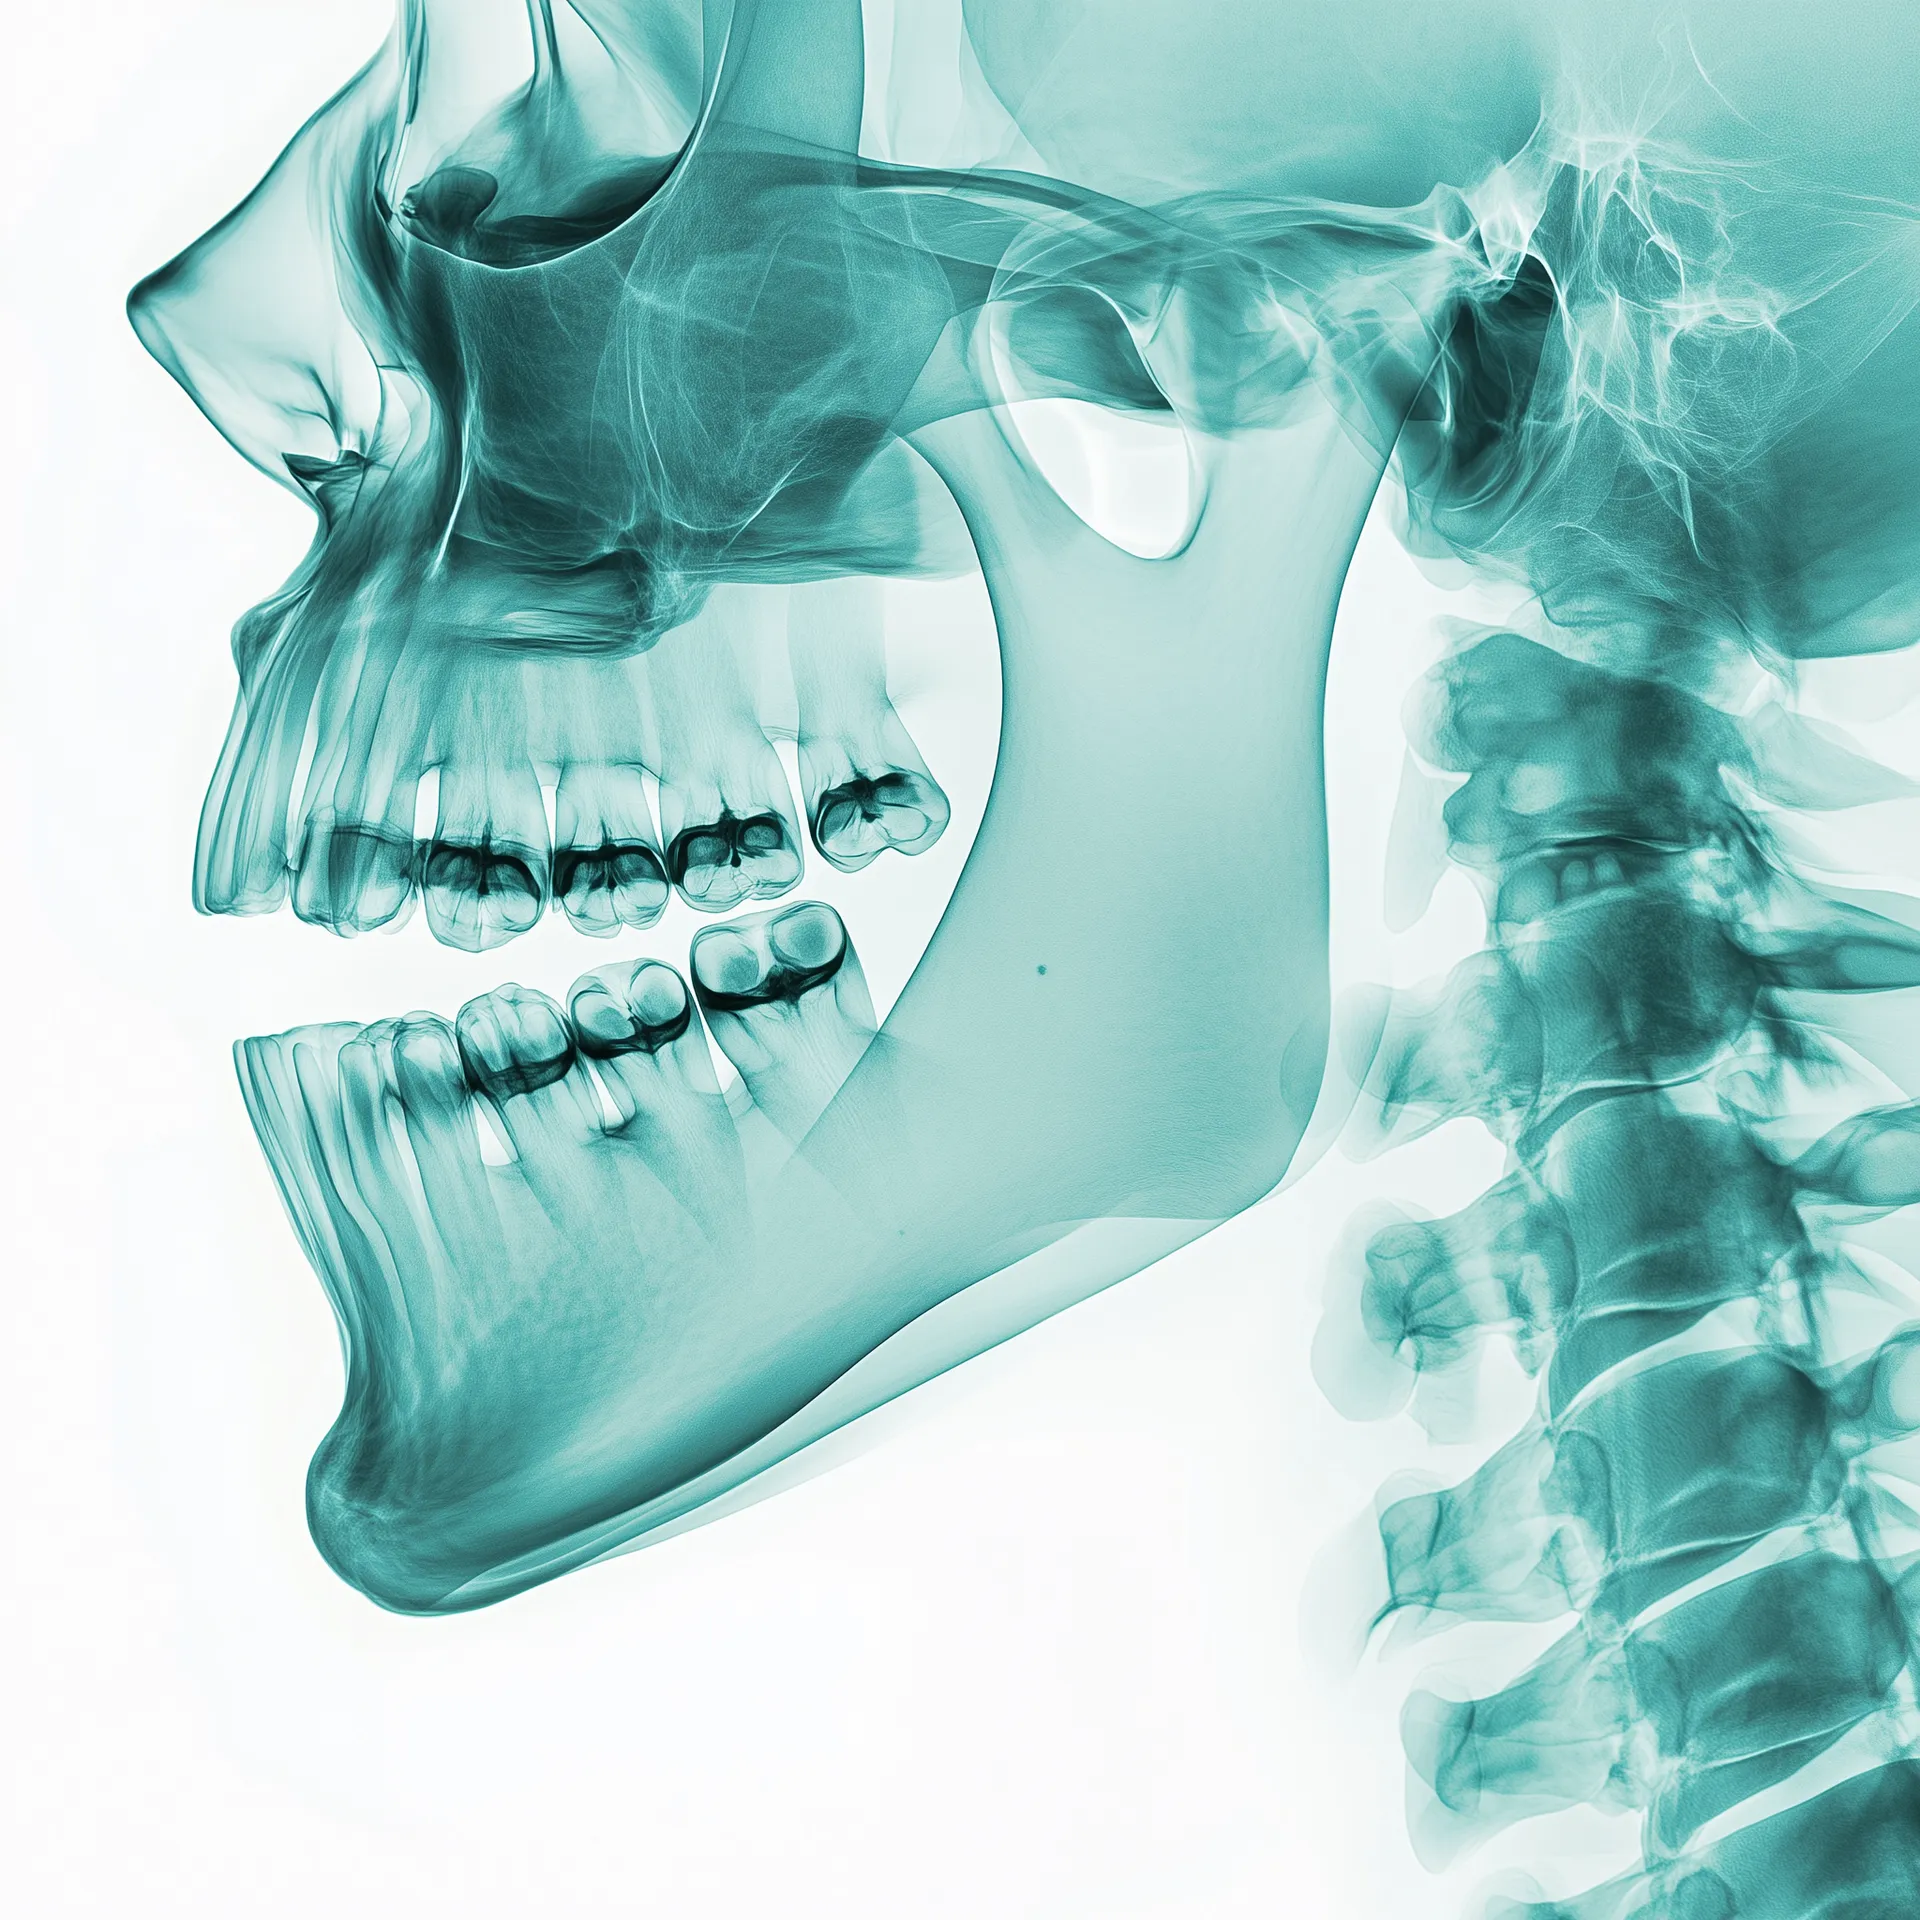

How Improper Jaw Development Affects Speech and Overall Health

When we think about speech development, we often focus on language skills and pronunciation practice. However, many parents and even some healthcare professionals overlook a critical factor—jaw development. The alignment of a child’s jaw directly influences their ability to produce clear, accurate sounds, impacting not only speech clarity but also other essential functions like swallowing, eating, and breathing.

The jaw plays a crucial role in supporting the tongue’s movements and positioning. When a child’s jaw is underdeveloped or misaligned, the tongue may not rest properly on the roof of the mouth. This can create difficulties in forming sounds, leading to speech impediments such as lisps or unclear articulation. Some of the most common effects include: